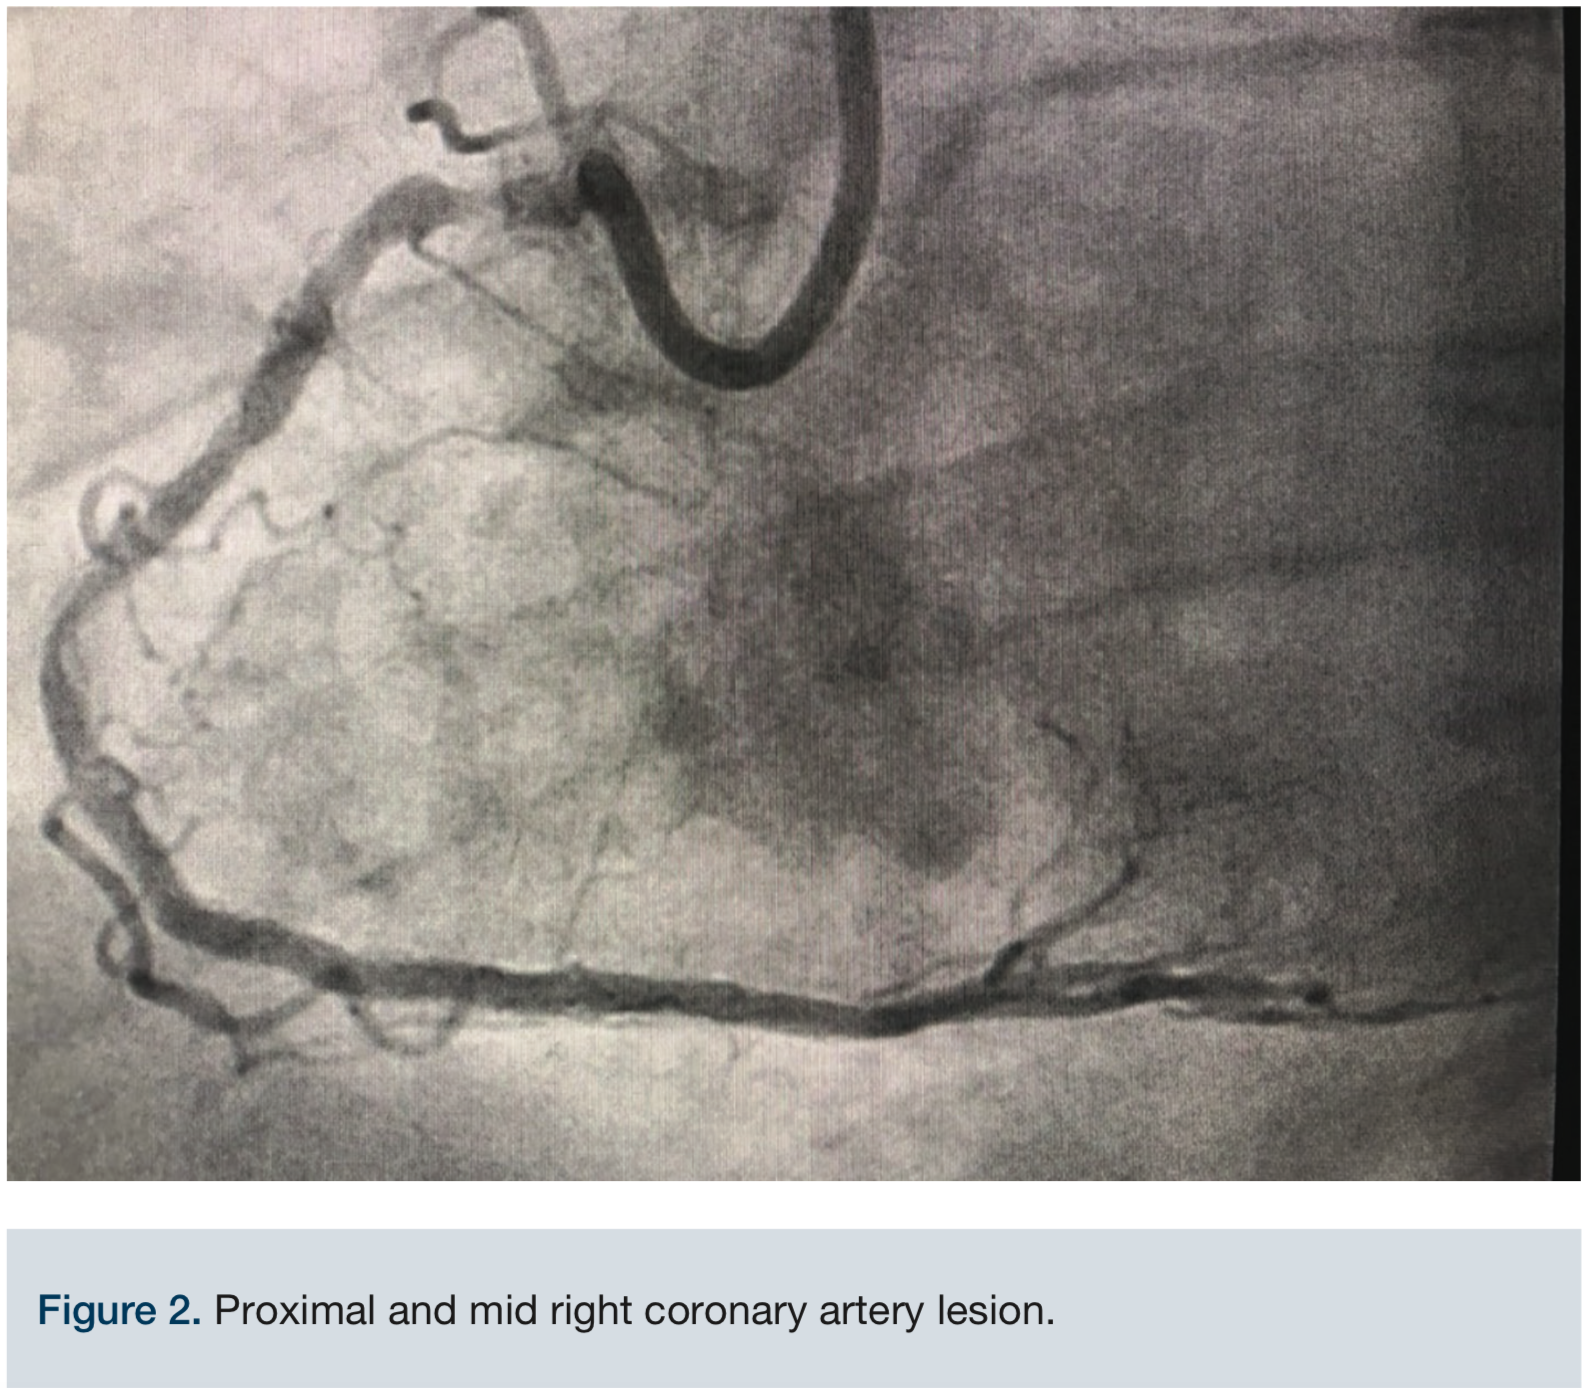

Access was obtained via the right common femoral artery. The initial lesion in the mid proximal RCA can be seen in Figure 2. An 8 French (Fr) long Destination sheath (Terumo) was used for maximum support, and a 0.75 Amplatz left (AL) 2 Guide catheter (Boston Scientific) was used for access support and assistance. A Balance Middleweight (BMW) wire (Abbott Vascular) was initially used to advance the catheter into the target artery. We switched to a 300 cm PT choice wire (Boston Scientific) in an attempt to cross the existing stent lumen, with the use of a 6 Fr Guideliner (Teleflex) for additional support. A 2.5 mm x 12 mm balloon (Medtronic) failed to cross the mid RCA stent fracture and ISR. The two markers on the balloon created a too-large catheter diameter, so a 1.25 mm x 12 mm single marker balloon (Medtronic) was chosen instead and successfully crossed. The balloon was inflated to 20 atmospheres (atm) and removed. A second attempt to pass the original 2.5 mm x 12 mm balloon (Medtronic) once again failed. The ELCA catheter was positioned just proximal to the mid RCA ISR within the fractured stent lumen. We started with an 0.9 laser catheter with the tip terminating just proximal to the ISR. An initial fluence of 45 mJ/mm2 was applied and gradually increased to a fluence of 80 mJ/mm2 for a total of almost 5 minutes while the tip was still positioned proximally to the ISR. The laser then was able to advance through the obstruction and was removed. Over the wire, a 2.5 mm x 12 mm balloon was inflated up to 20 atm for 25 seconds and then replaced with a 3.0 mm x 20 mm balloon (Medtronic) inflated to nominal pressure. The same 3.0 mm balloon was used at the very proximal aspect of the ISR as a pre-dilation before two drug-eluting stents (DES) were placed: a 3.0 mm x 18 mm Onyx DES (Medtronic) at the mid RCA and a second 3.0 mm x 30 mm Onyx DES at the proximal to mid RCA. The 3.0 mm x 18 mm Onyx DES stent was deployed at 22 atm for 15 seconds and the 3.0 mm x 30 mm Onyx DES was deployed 20 atm for 10 seconds. Post stent deployment, angiography clearly demonstrated reduction of the stenosis from approximately 99% to <10% at the site of the original stenosis in the proximal to mid RCA. At the end of the procedure, Thrombolysis In Myocardial Infarction (TIMI)-III flow was achieved (Figure 3). Inline flow was successfully restored across the entire RCA. The procedure was uncomplicated, but required the use of significant amounts of contrast (500 mL) and fluoroscopy (81.1 minutes). The patient was discharged the following day without incident, and has thus far remained asymptomatic throughout his follow-up with his referring cardiologist.